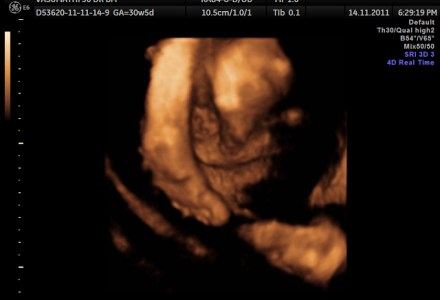

Congenital Diaphragmatic Hernia ( CDH ) and Fetal Hydronephrosis